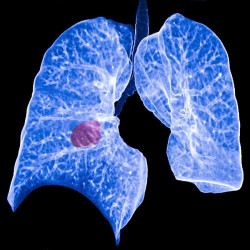

Descubren una segunda vía clave en el crecimiento de las células madre del cáncer de colon

En una investigación revolucionaria sobre el cáncer de colon, los científicos del Instituto de Investigación y Centro Oncológico Helen F. Graham de ChristianaCare, en Estados Unidos, han descubierto un vínculo entre dos vías de señalización clave que son cruciales para el desarrollo y crecimiento del cáncer de colon, según publican en la revista `PLOS ONE`.